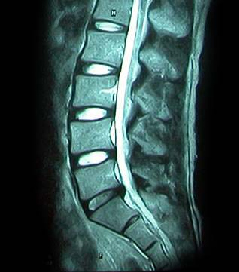

• 척추 방사선 사진2

64세 여자환자는 2개월 전부터 요통과 다리 바깥쪽과 발등, 종아리 뒤쪽으로 저린 감각이 심해져서 개인병원에 들러 평가 및 물리치료를 받았으나 별다른 호전이 없고, 1주일 전부터는 허리를 숙이거나 물건을 들 때, 오래 걸을 때 통증이 더 심해져서 본원을 방문하였다. 12년전 집안일을 심하게 하고 난 후부터 간헐적인 요통을 발생하였으며, 별다른 치료 없이 지냈으며, 4년전 무거운 물건 들고 난 후 심하게 요통과 둔부의 통증까지 발생하여 MRI 촬영상 L1-2, L3-4-5, L5-S1 HNP와 Lt. L4 & both L5 nerve compression, Lt. S1 nerve compression 진단받고 Epidural steroid injection을 받고 통증 경감되었고, 간헐적으로 통증이 발생하였으나 별다른 치료 없이 헬스클럽에서 지속적인 운동으로 관리하였다.